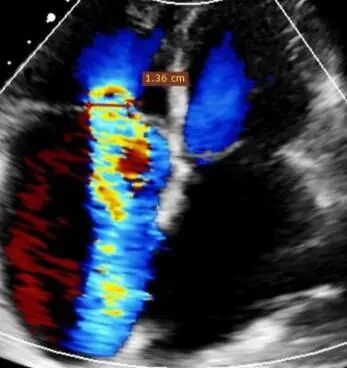

- Massive tricuspid regurgitation (5+, mean vena contracta 14mm);

- Regurgitant orifices located at antero-septal, central, and postero-septal regions, with a significant gap at the antero-septal region (antero-septal gap 9.1mm), leaflet tethering (tethering height approximately 9mm);

- Tricuspid annular dilation (mean annulus diameter: 43mm);

1. Regurgitation Effect: Reduced from massive (5+) to moderate (2+).

Preoperative

Postoperative